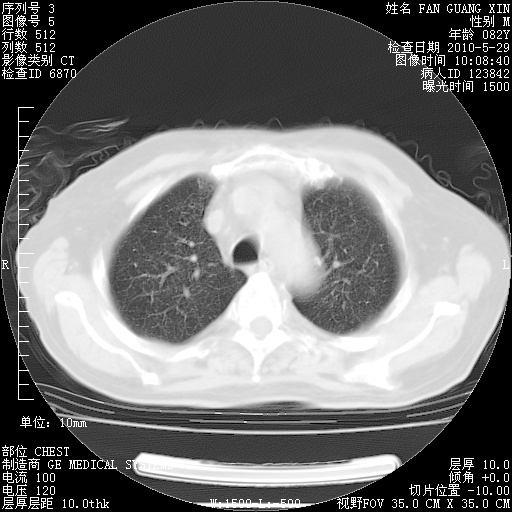

再治疗10天后的肺部CT

再治疗10天后的肺部CT 纵膈窗

阅读此次胸部CT,肺间质渗出性改变较入院时有吸收。目前从体温、白细胞、中性分叶明显增高,肯定存在细菌感染(发生医院感染哦,若无消化道及泌尿系统等感染的依据,肺部感染可能大)。若你院头孢哌酮舒巴坦钠耐药率较高,同意你的方案,若48小时体温仍高,可考虑使用碳青霉稀类抗菌药物,同时可予超声雾化、注意滴数时加大液体量。白蛋白33.30g/L较低哦,需加强营养等支持治疗。